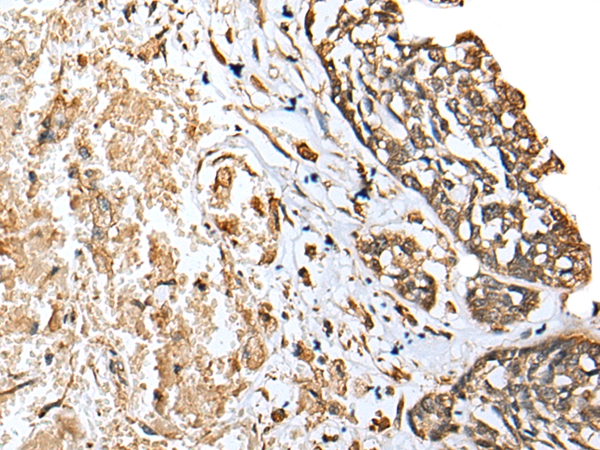

Immunohistochemical analysis of paraffin-embedded Human prostate cancer tissue using #42964 at dilution 1/25.